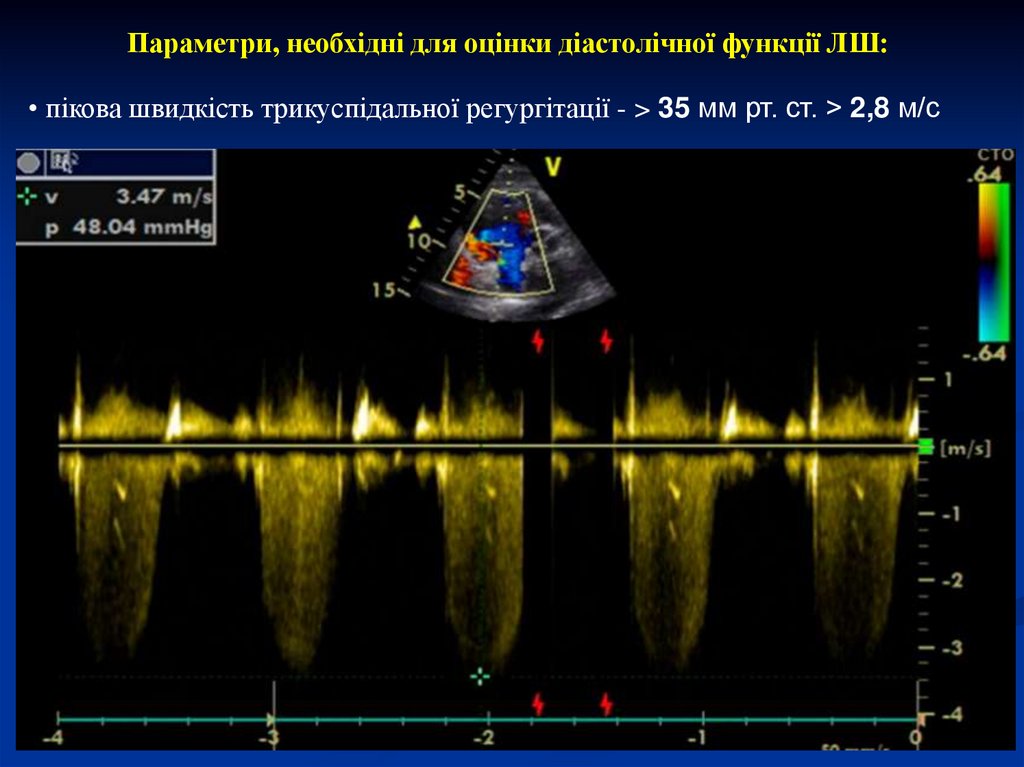

Параметри, необхідні для оцінки діастолічної функції ЛШ:

• пікова швидкість трикуспідальної регургітації - > 35 мм рт. ст. > 2,8 м/с